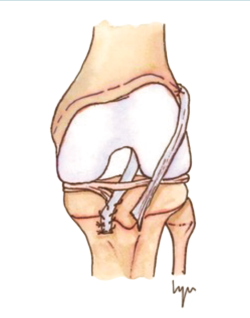

El tratamiento conservador, mediante reposo deportivo y rehabilitación, con una incorporación gradual a la práctica deportiva, pretende recuperar la actividad previa evitando las posibles lesiones fisarias iatrogénicas asociadas a las técnicas de reconstrucción del LCA convencionales, que pudieran producir dismetrías y alteración de los ejes(4,5,6,7,8). Sin embargo, este enfoque subestima las posibles lesiones meniscales y condrales futuras relacionadas con la inestabilidad secundaria. Por otro lado, el tratamiento quirúrgico intenta prevenir estas lesiones meniscales y condrales, secundarias a la inestabilidad que se produce tras la lesión del LCA, asumiendo el riesgo potencial de lesiones fisarias. Atendiendo a estas premisas, en los últimos años se han descrito técnicas específicas para pacientes esqueléticamente inmaduros que minimizan la agresión de la placa fisaria(9,10,11,12,13,14,15,16)(Figura 1).

Figura 1. Esquema de los tipos de reconstrucción del ligamento cruzado anterior (LCA) según la relación con la fisis. A: epifisaria; B: transfisaria.